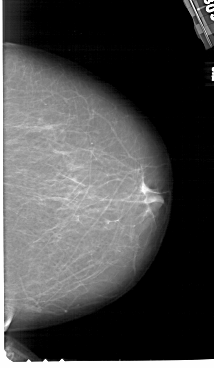

A_1108_1.RIGHT_CC

RIGHT_CC LINES 6616 PIXELS_PER_LINE 3841 BITS_PER_PIXEL 12 RESOLUTION 43.5 NON_OVERLAY

FILE: A_1108_1.LEFT_CC.OVERLAY

TOTAL_ABNORMALITIES 1

ABNORMALITY 1

LESION_TYPE CALCIFICATION TYPE PUNCTATE DISTRIBUTION CLUSTERED

ASSESSMENT 4

SUBTLETY 2

PATHOLOGY MALIGNANT

TOTAL_OUTLINES 1

BOUNDARY